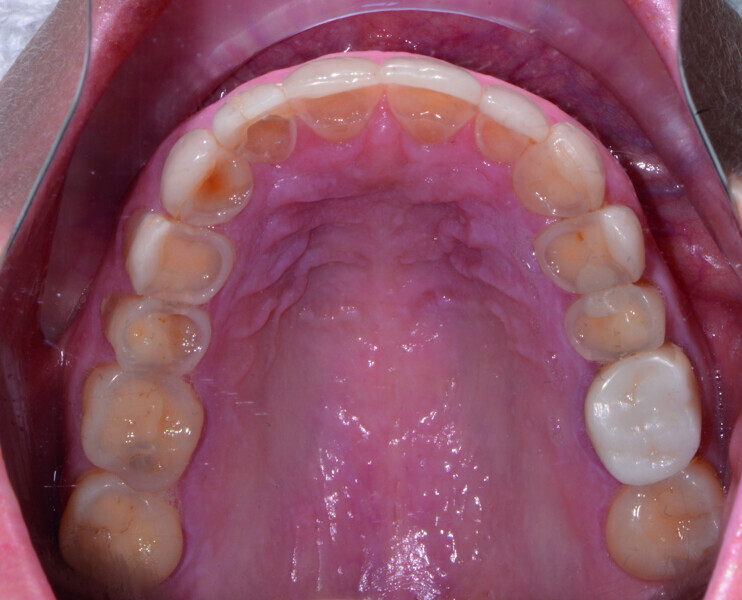

Restoring function and aesthetics with monolithic zirconia restorations